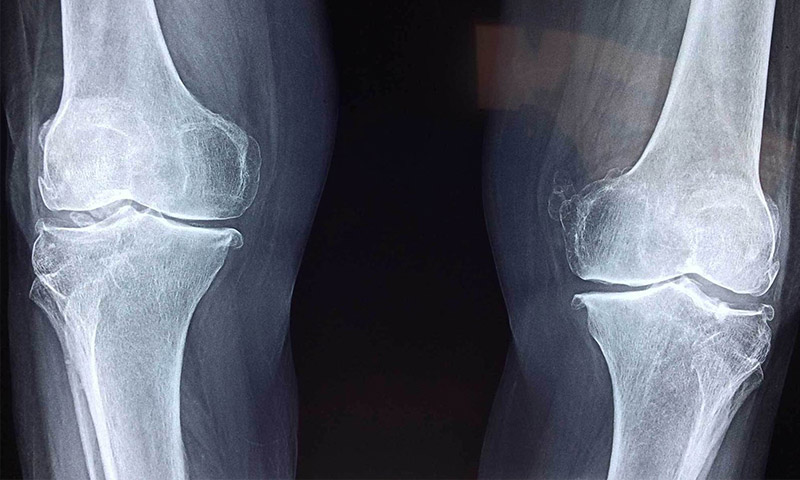

- اشعه ایکس زانو

این آزمایش پارگی منیسک را نشان نخواهد داد. با این حال، مشخص می کند که آیا علل دیگری مانند آرتروز برای درد زانو وجود دارد یا خیر. - MRI